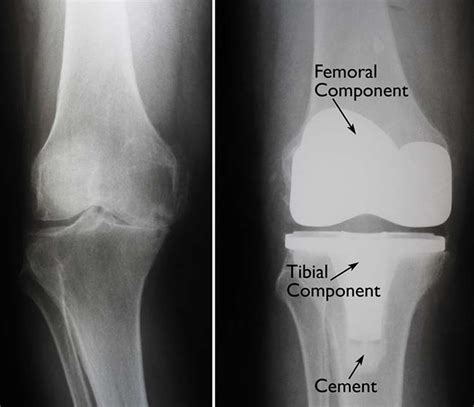

Total knee arthroplasty, or knee replacement, is a highly successful surgery designed to relieve pain and restore function in diseased or damaged knee joints. By looking at Knee Replacement Images, patients can see how an orthopedic surgeon removes the damaged cartilage and bone from the surface of the knee joint and replaces them with artificial components. These components are meticulously crafted to mimic the natural movement of a healthy knee.

The surgery generally involves three primary parts:

• The Femoral Component: A metal piece that attaches to the end of the thigh bone (femur).

• The Tibial Component: A metal tray that sits on top of the shin bone (tibia).

• The Patellar Button: A plastic piece that replaces the surface of the kneecap.